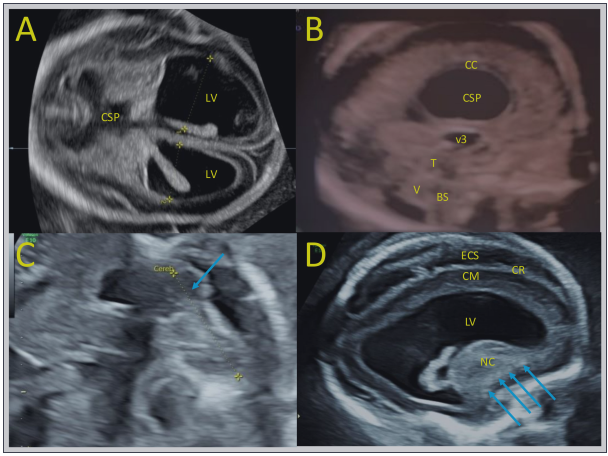

由于胎儿异常,羊膜穿刺术在22 wg时进行。核型为46,XX。阵列CHG未检测到胎儿基因组中的微缺失或微重复,羊水中的CMV PCR为阴性。接下来在25和28 wg时进行的超声波检查发现了类似的大脑异常,脑积水增加导致右半球脑实质极度变薄,而在28 wg时头围为292 mm的巨头畸形(>97百分位)。最后一次超声检查还发现视交叉发育不全,特别影响右视神经和后束(视交叉直径为5.2 mm,右视神经直径为2.0和1.8 mm,图2)。脑外检查发现心脏肿大、轻微心包积液、肝脏肿大和中度腹水。大脑中动脉的收缩速度为56cm/s,相当于1.5 mom,提示胎儿贫血。

图2. 孕25和28周胎儿超声检查